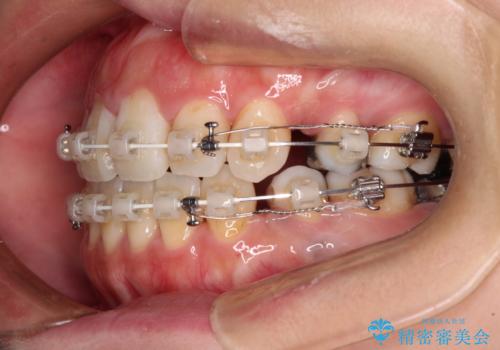

出っ歯と奥歯の欠損 ワイヤー矯正とインプラント治療

口元の突出感改善には、上下左右の第一小臼歯4本を抜歯し、奥歯の欠損部には矯正治療の途中でインプランを埋入していくこととしました。

矯正治療の後半にインプラント埋入を行うことで、トータルの治療期間を短縮することができました。